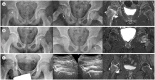

Developmental dysplasia of the hip is a condition characterized by hip joint instability due to acetabular dysplasia in infancy, necessitating precise ultrasound examination. Legg-Calvé-Perthes disease is caused by a temporary disruption in blood flow to the femoral head during childhood, progressing through avascular, fragmentation, re-ossification, and residual stages. Slipped capital femoral epiphysis is a condition where the femoral head shifts medially along the epiphyseal line during adolescence due to stress, such as weight-bearing. Differentiating between transient hip synovitis and septic arthritis may require joint fluid aspiration. Osteomyelitis can be associated with soft tissue edema and osteolysis. When multiple lesions are present, it is essential to distinguish between Langerhans cell histiocytosis and metastatic neuroblastoma. This review will introduce imaging techniques and typical findings for these conditions.